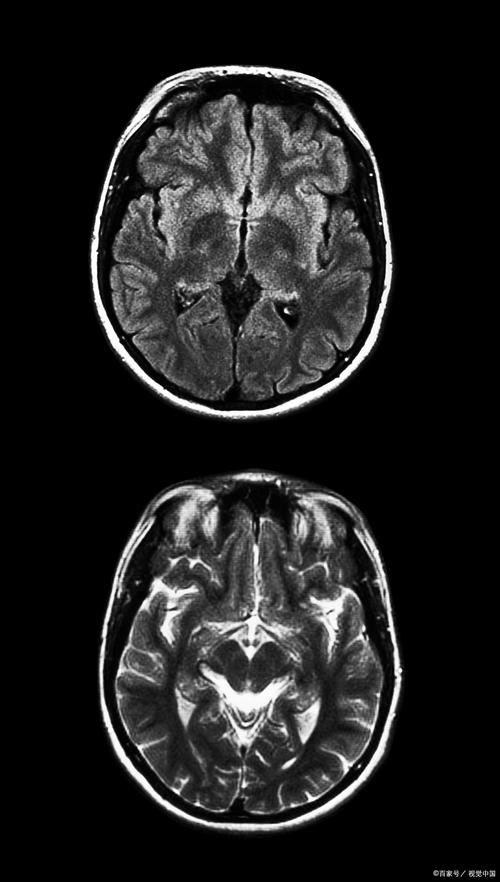

局限性:对早期梗死不敏感 脑梗死后,脑细胞发生缺血坏死的改变需要时间,在发病后的6小时内,CT上可能完全看不出异常,或者只有一些非常细微的征象(如脑沟变浅、密度轻微减低),需要经验丰富的放射科医生才能发现,这就是为什么很多患者发病初期CT正常,医生仍高度怀疑脑梗,并会建议做进一步检查(如MRI)。

(图片来源网络,侵删)